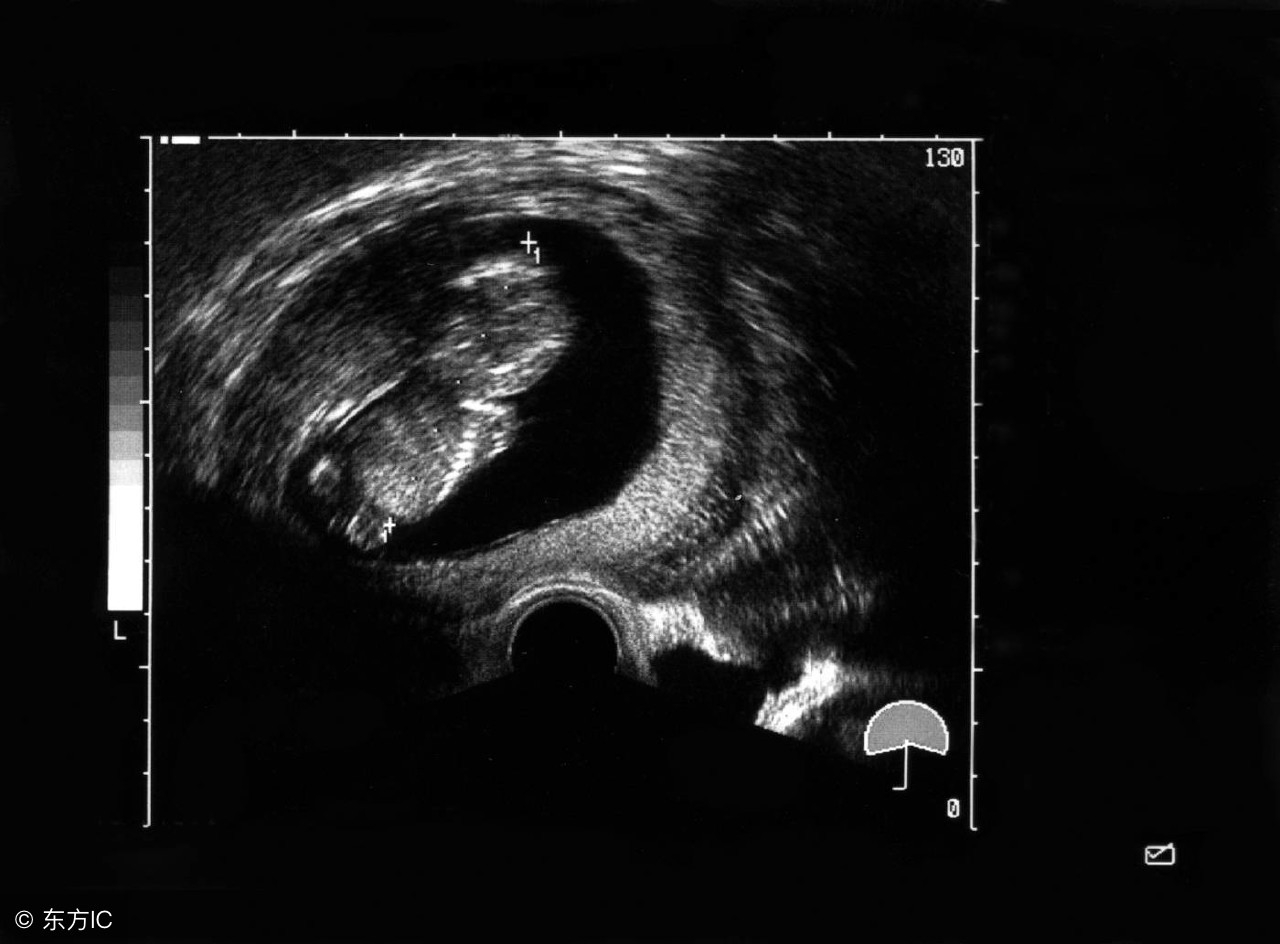

B超测试宝宝比孕周小的情况非常多见,很多朋友都提到这个问题。其实,B超测量和实际孕周有差距都是正常的。

看过B超检查过程就会发现,测量胎儿的各部位尺寸是需要丰富经验的,我们普通人确实看不明白,不知道哪是哪。反正就看医生在一个部位画上一些红色的线条,边上的辅助医生就给输入一些数据,有时还看他们讨论一番,最终给我们出具一个结果。画线的过程就是产生误差的过程。